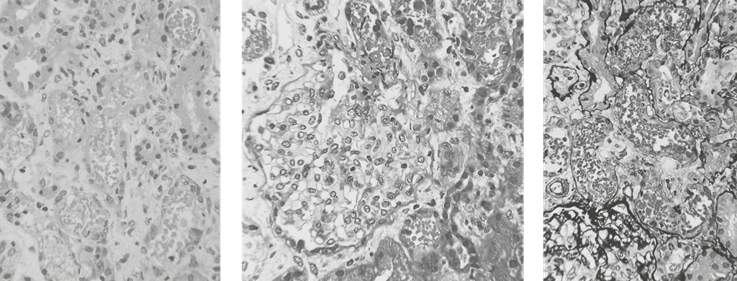

Ante deterioro progresivo de función renal, llegando a requerir soporte dialítico, se realiza biopsia renal evidenciando necrosis tubular aguda (Figura 1).

Figura 1 Tejido renal corticomedular. Se observa daño tubular agudo, con múltiples cilindros granulares de color rojizo que podrían corresponder a hemoglobina o mioglobina, no se descarta una nefritis tubulointersticial aguda asociada. Se observan cortes histológicos con tinción de Hematoxilina-Eosina, tricrómico y plata metenamina. Fuente: Resultado histopatológico de la paciente Adicionalmente se solicitaron pruebas de autoinmunidad sin resultado patológico, electroforesis de proteínas el cual no evidencia pico en región gamma y Coombs mono específico evidenciando IgG ++.